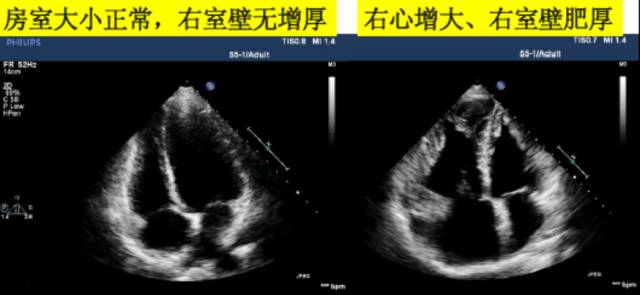

4、右心室大小的评估

由于右心室的几何构型复杂、定量评估困难,目前临床上多采用右心室的面积或内径与左心室对比来作出定性评价。

7、右室壁厚度的测量

测量位置:常用胸骨旁长轴与剑突下四腔心切面。

测量时相:舒张末期。

若合并有心包增厚时,难以确定;超过5mm即为右心室增厚,在没有其他病理改变的情况下提示右室压力负荷过重。

ASE推荐采用剑突下四腔心切面测量右心室壁厚度,因其重复性和与右心室收缩压的相关性较好。